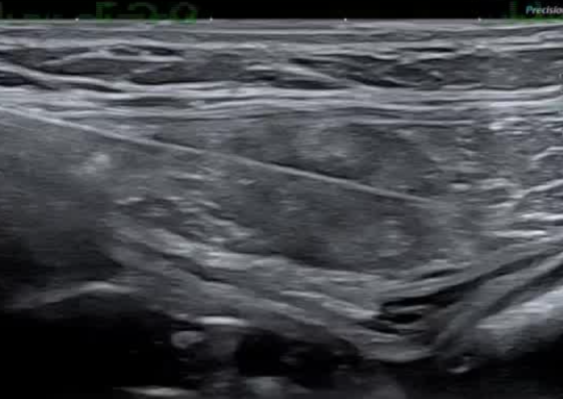

影像引导方式:超声和横断面成像(CT或MRI)结合是最常用的影像引导方式(10/16,62.5%)。

保护措施:几乎所有干预都需要辅助保护措施,其中水分离术(13/16,81.3%)和水分离术与温盐水填充手套的皮肤保护结合(9/16,56.3%)是最常见的保护措施。

通常需要三根布针

endomuscular